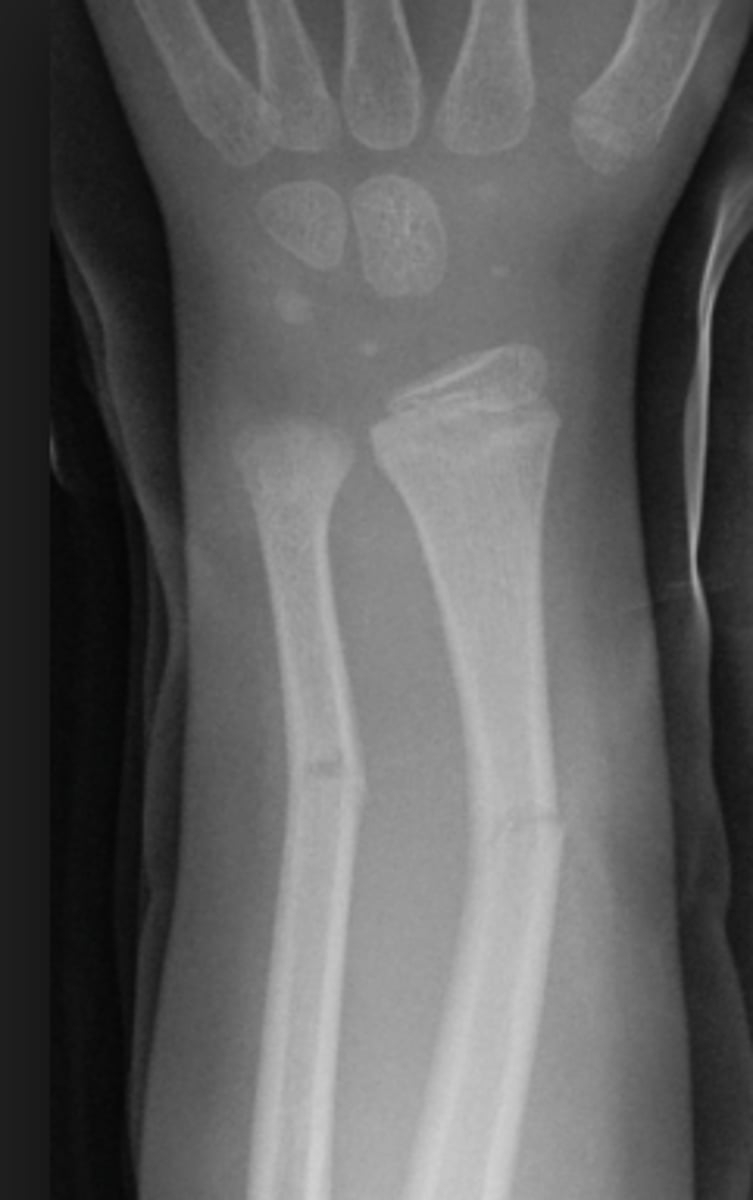

avulsion fracture

Fracture due to tendon/ligament pulling off small piece of bone

greenstick fracture

Incomplete break, causing bending of bone

torus fracture

- AKA: impacted, buckle

- Broken bone ends driven into one another